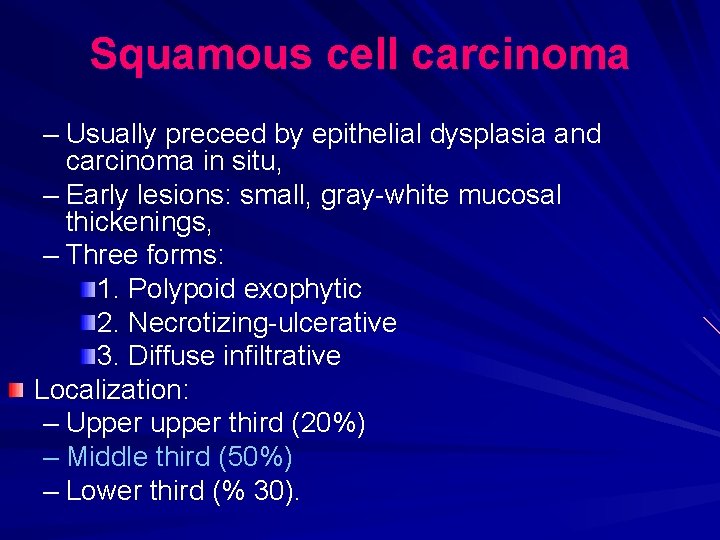

Squamous cell carcinoma – Usually preceed by epithelial dysplasia and carcinoma in situ, – Early lesions: small, gray-white mucosal thickenings, – Three forms: 1. Polypoid exophytic 2. Necrotizing-ulcerative 3. Diffuse infiltrative Localization: – Upper upper third (20%) – Middle third (50%) – Lower third (% 30).